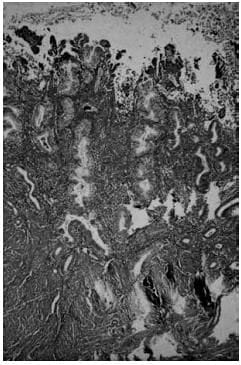

Histological appearance of

(a) late secretory

(b) menstrual endometrium